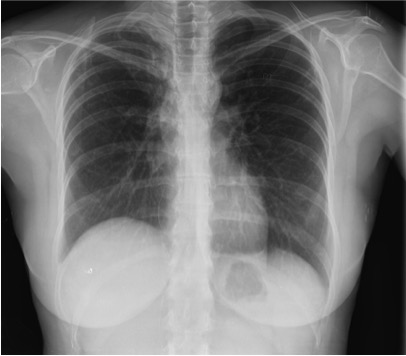

Solución: Es un estudio Normal. Silueta cardiomediastínica y parénquimas pulmonares sin alteraciones significativas.

En esta sección nos dedicaremos a la radiografía simple del Tórax. Iremos introduciendo casos de manera periódica con diversa semiología, así el objetivo es día a día quedarnos con un concepto radiológico fundamental, que luego nos sea de ayuda en nuestra práctica clínica rutinaria.

Empecemos, ¿qué ves?

- Comprobar que la placa está bien centrada e inspirada (6 arcos costales anteriores ó 9 posteriores).

- Abdomen y Diafragma

- Partes blandas y estructura ósea.

- Mediastino con silueta cardiaca.

- Parénquimas pulmonares (por separado)

- Comparar un pulmón con otro.

Seguir esta sistemática, dejando el pulmón para el final no nos olvidaremos de lo más importante.

Regla: Acaso Tiene Mucha Patología Pulmonar (Abdomen, Tejidos blandos y hueso, Mediastino, Pulmón por separado, Pulmón bilateral)

Nota: ¡¡¡No olvidar la placa lateral!!! La regla a seguir es la misma. Leer abdomen y diafragma, examinar parte posterior, tejidos blandos y subir por la columna; tráquea y descender por mediastino. Finalmente pulmones.